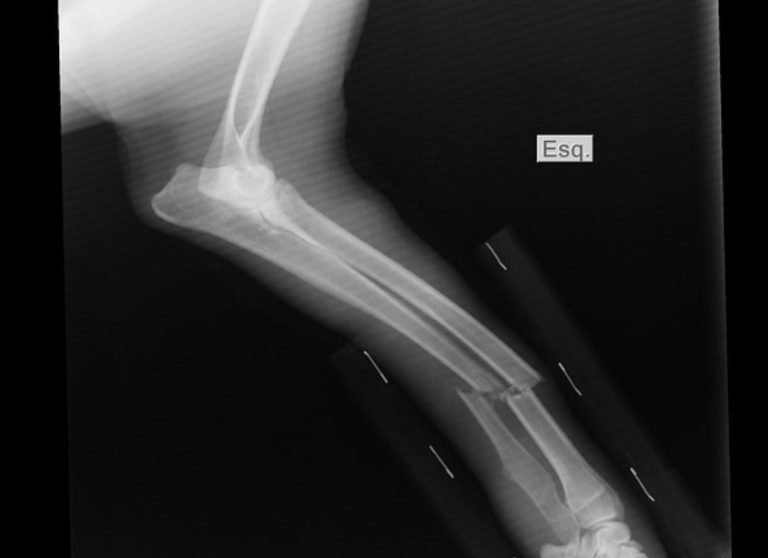

Una mujer de 40 años resultó con una fractura en su muñeca izquierda luego que un hombre la golpeara con un fierro tras un choque.

En medio de los insultos, el hombre la golpeó y le produjo la fractura, según informó Crónica.